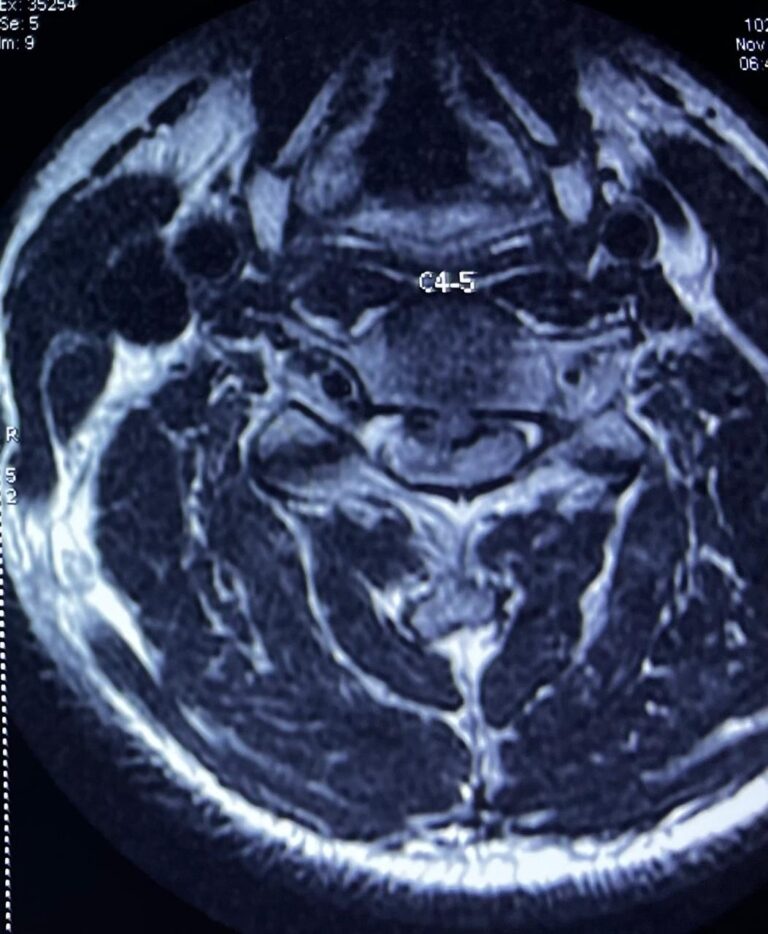

What is Cervical Myelopathy? Literally cervical myelopathy means dysfunction of the spinal cord in the cervical region (neck). The dysfunction is due to compression of the spinal cord in the neck...